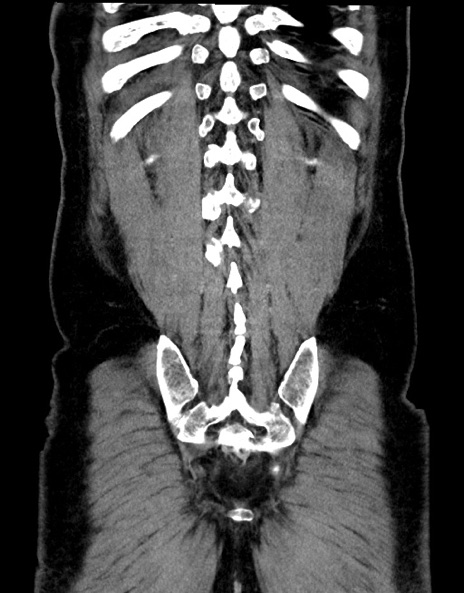

横断像